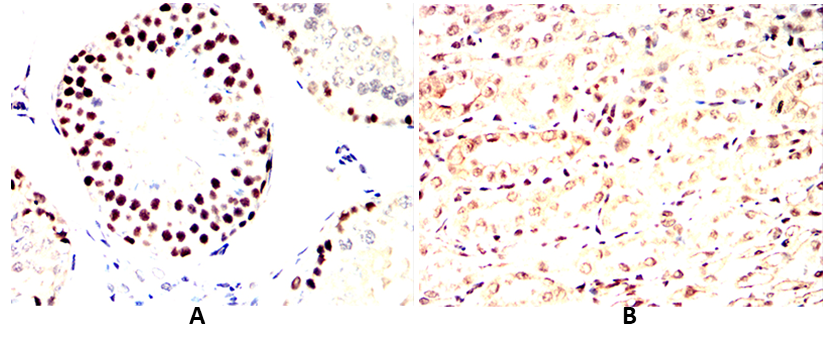

Immunohistochemical analysis of paraffin-embedded Mouse colon(A) Mouse testis(B) using PCNA mouse mAb with DAB staining.